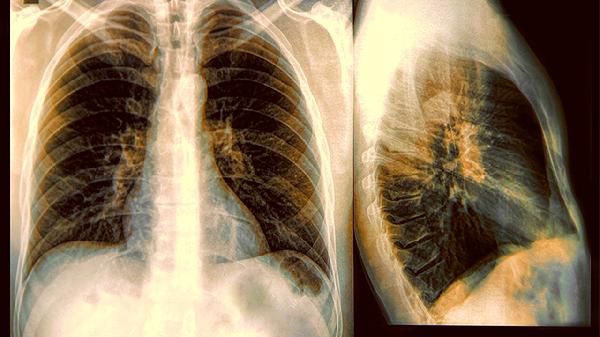

大约有三成的变异性哮喘患者,肺功能检查结果看起来是正常的,需要通过支气管激发试验才能确诊。由于其症状和慢性支气管炎、胃食管反流等疾病很相似,很容易被误诊。尤其是咳嗽型哮喘患者,有时候会被当作普通感冒来治疗,耽误了最佳干预时间。